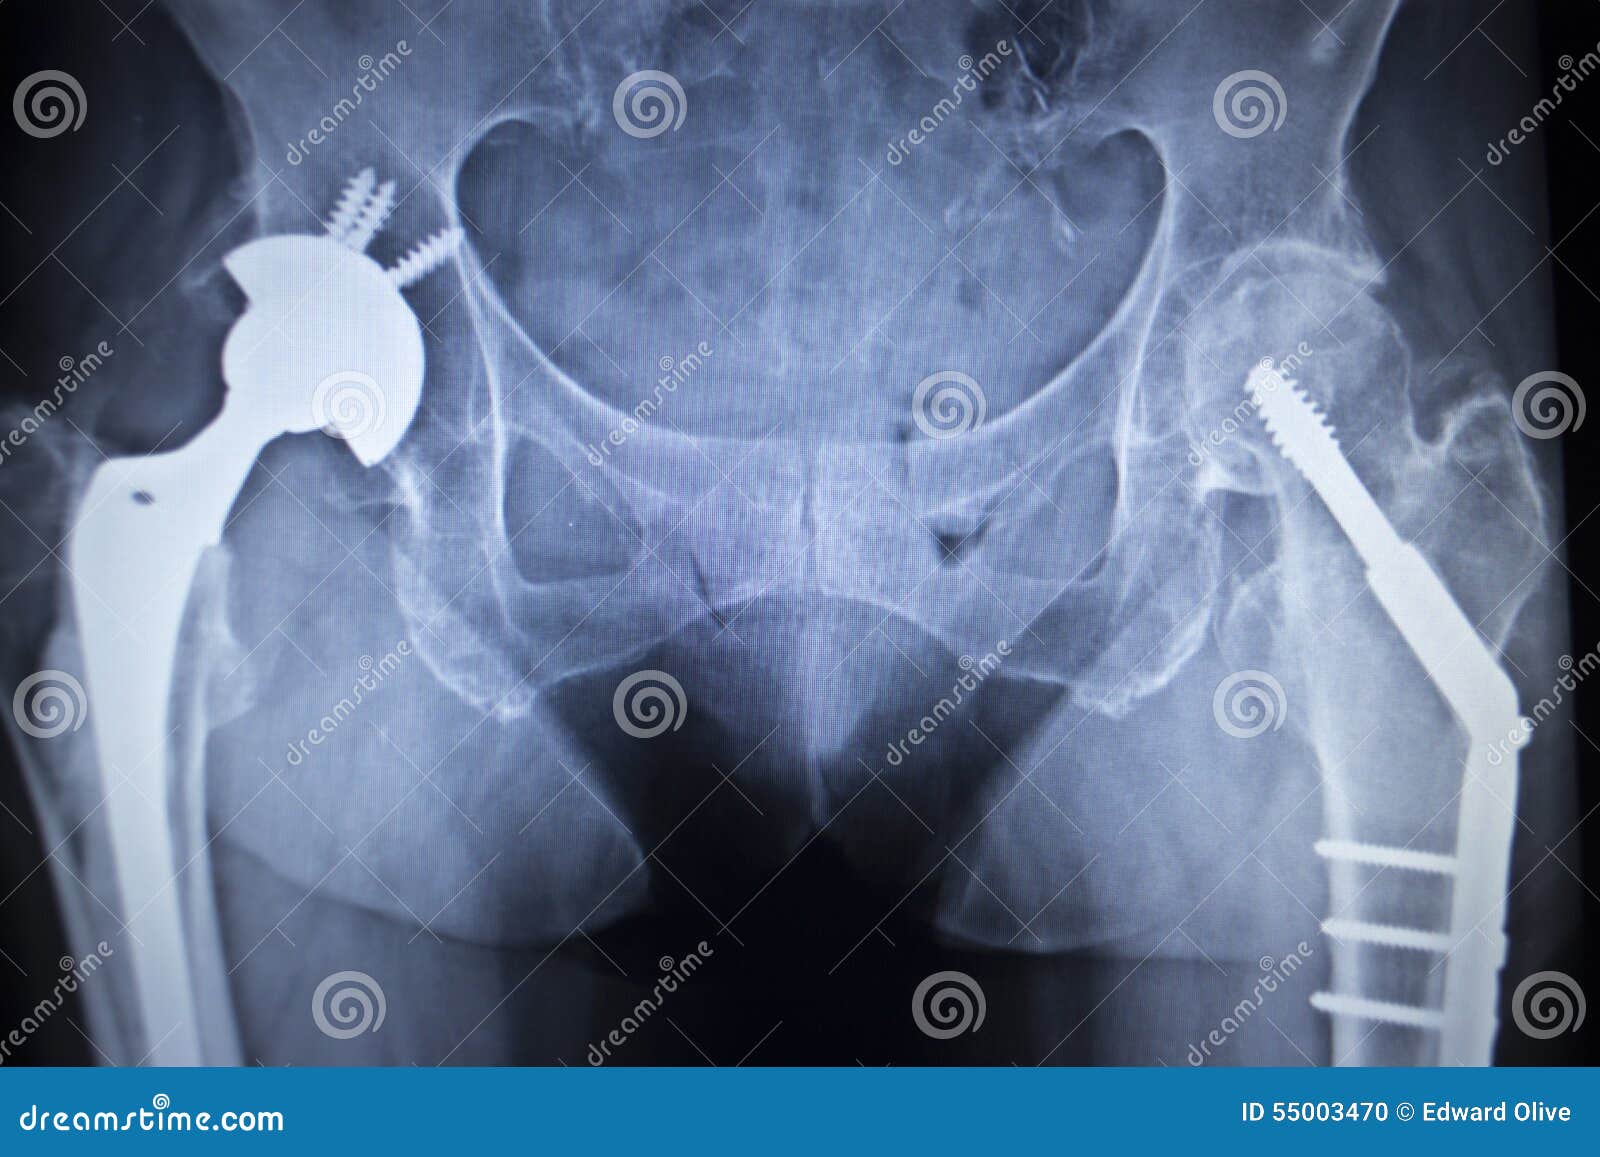

Замена таз сустава

Замена таз сустава 113 фотографий